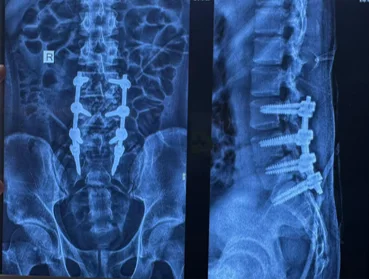

Before & After Clinical Gallery

We showcase real patient cases (with consent), including:

• Pre- and Post-operative MRIs and X-rays

• Disc Herniations, Stenosis, and Spondylolisthesis cases

• Visible improvement in alignment and decompression

Before

After